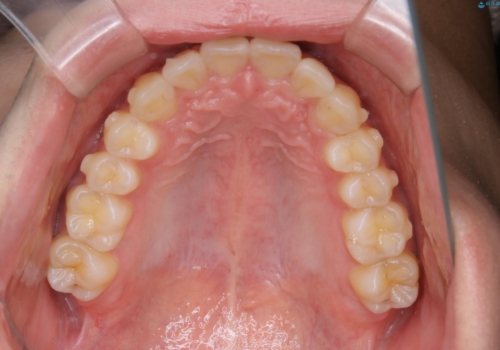

- 口元の突出感は気にならないが、上の前歯の角度と、下の前歯のがたつきが気になるとご相談にいらした方です。なるべく費用や治療期間を抑えて治療したいとのご希望に合わせて治療を計画しました。

この患者様への治療方針として、奥歯から少しずつ歯を移動させる方法と、歯をわずかに削って並べる方法とをご提案しました。短期間での治療を望まれたため、歯をサイズダウンさせて歯を並べました。わずかではあるものの、削った歯は元には戻せないことを十分ご説明し、ご理解ご了承を頂いた上で治療を行いました。